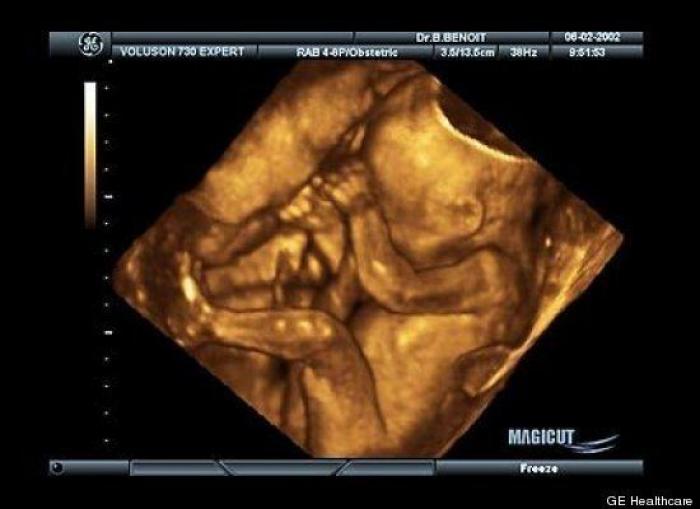

En esta galería puedes ver en fotos como es el desarrollo de un feto de semana en semana:

Desarrollo del feto, en fotos